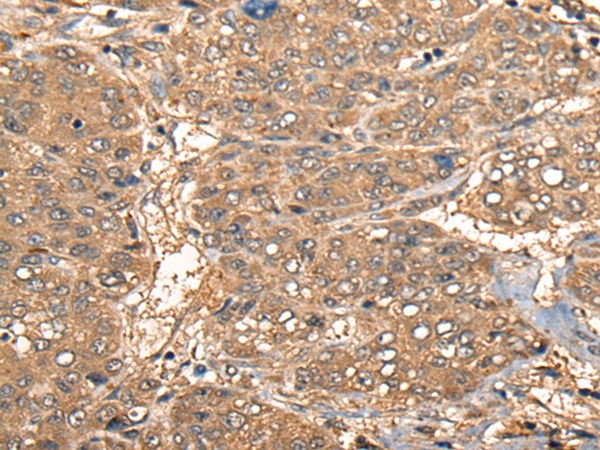

The image on the left is immunohistochemistry of paraffin-embedded Human liver cancer tissue using 46423(CCL27 Antibody) at dilution 1/55, on the right is treated with synthetic peptide. (Original magnification: x200)